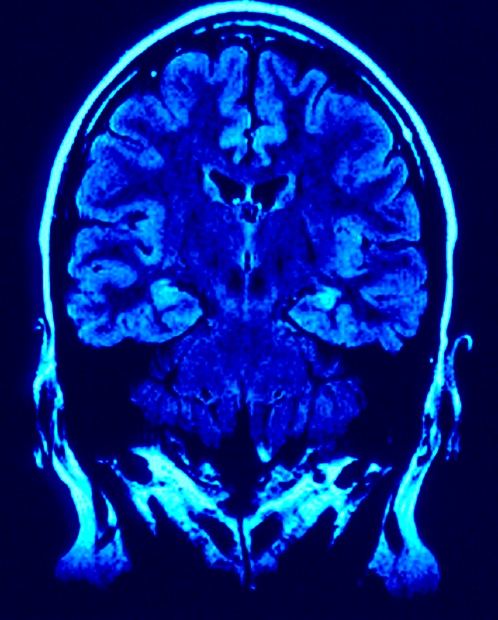

Przestępstwa można przewidzieć – twierdzą neurolodzy z USA. Wystarczy do tego skan mózgu. W ten sposób wizja filmu ("Raport mniejszości") Stevena Spielberga z Tomem Cruisem w roli głównej przestaje być fikcją.

Eksperci z Sieciowego Instytutu Badań Umysłu w Nowym Meksyku prowadzili badania z udziałem prawie 100 więźniów, których mózgi poddano skanowaniu rezonansem magnetycznym. Na podstawie szczegółowych analiz stwierdzono, że można przewidzieć potencjalne zagrożenie popełnienia czynów przestępczych. Zespół prowadzony przez Kenta Kiehla zbadał u więźniów przednią korę obręczy (ACC) - obszar położony w przedniej części mózgu, odpowiedzialny za podejmowanie decyzji. Naukowcy postawili sobie za cel analizę mózgów pod kątem „impulsywności podejmowanych decyzji”. Więźniowie zostali poproszeni, aby w momencie pojawienia się na ekranie komputera litery X szybko nacisnęli przycisk, a po pojawieniu się litery K nie robili niczego. Okazało się, że tylko 16% badanych nie nacisnęło przycisku po pojawieniu się litery K. Wyniki badania wykazały, że więźniowie popełniający więcej błędów mieli niższą aktywność w ACC. To wskazuje na wyższą skłonność do działania impulsywnego - bez zastanowienia. Następnym krokiem była obserwacja więźniów przez cztery lata po zwolnieniu. Z analiz dokumentacji policyjnej wynikało, że skazańcy, którzy mieli niższy poziom aktywności w ACC podczas badania przed komputerem, mieli zarazem większe ryzyko ponownego aresztowania w ciągu najbliższych czterech lat: 60 proc. osób z niższym poziomem aktywności ACC zostało ponownie aresztowanych. Zdaniem badaczy z Nowego Meksyku czynnikami ryzyka był wiek, nadużywanie narkotyków i alkoholu oraz cechy psychopatyczne. Mężczyźni z niższym poziomem aktywności ACC byli ponownie aresztowani 4,6 razy częściej niż pozostali. Przy tej okazji przypomniano badania z 2012 r. w których wykazano, że silnym predykatorem do określonych działań mogą być geny, oraz …. zbyt częste oglądanie telewizji, co ma prowadzić do wyobcowania i zachowań aspołecznych.